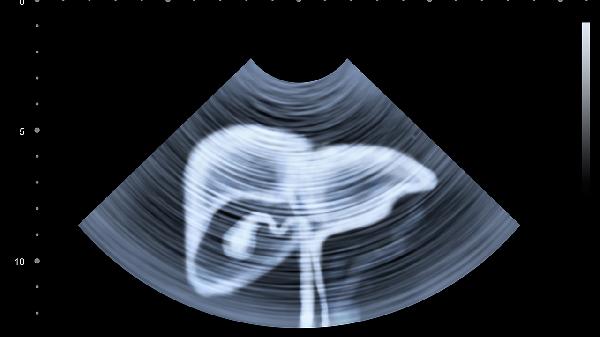

胆囊炎、胃炎也会引起类似疼痛,需要通过B超、CT等影像学检查鉴别。

即使肝功能正常,也要每6个月做一次甲胎蛋白和超声检查。